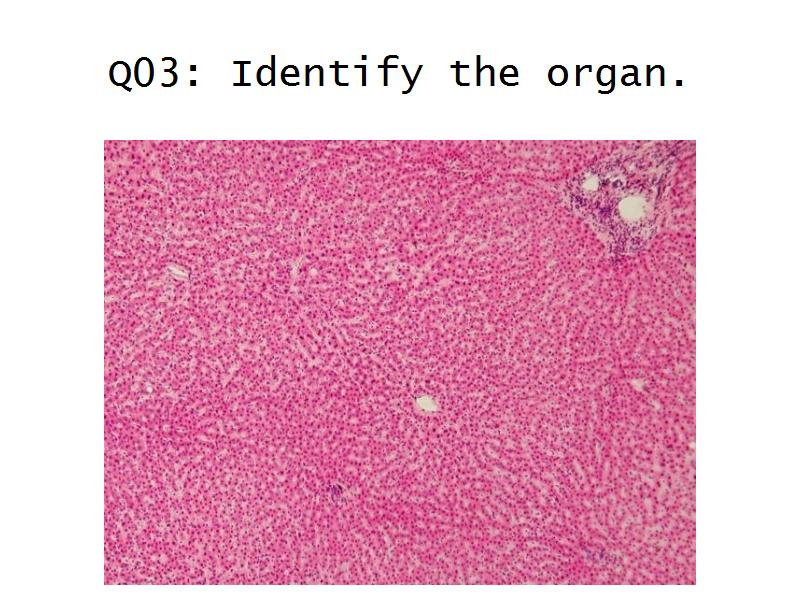

Kidney

And

Oral Cavity

Q13: Name 1 epithelium for each.

- Kidney =

- Liver =

Q13: Name 1 epithelium for each.

- Kidney = cuboidal, squamous

- Liver = squamous, cuboidal

Kidney